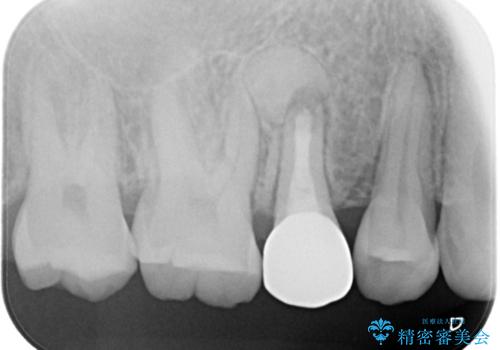

【根管治療】噛んだ時にしみる。最近になってズキズキ痛み、長引く痛みがある

担当医 河口智英